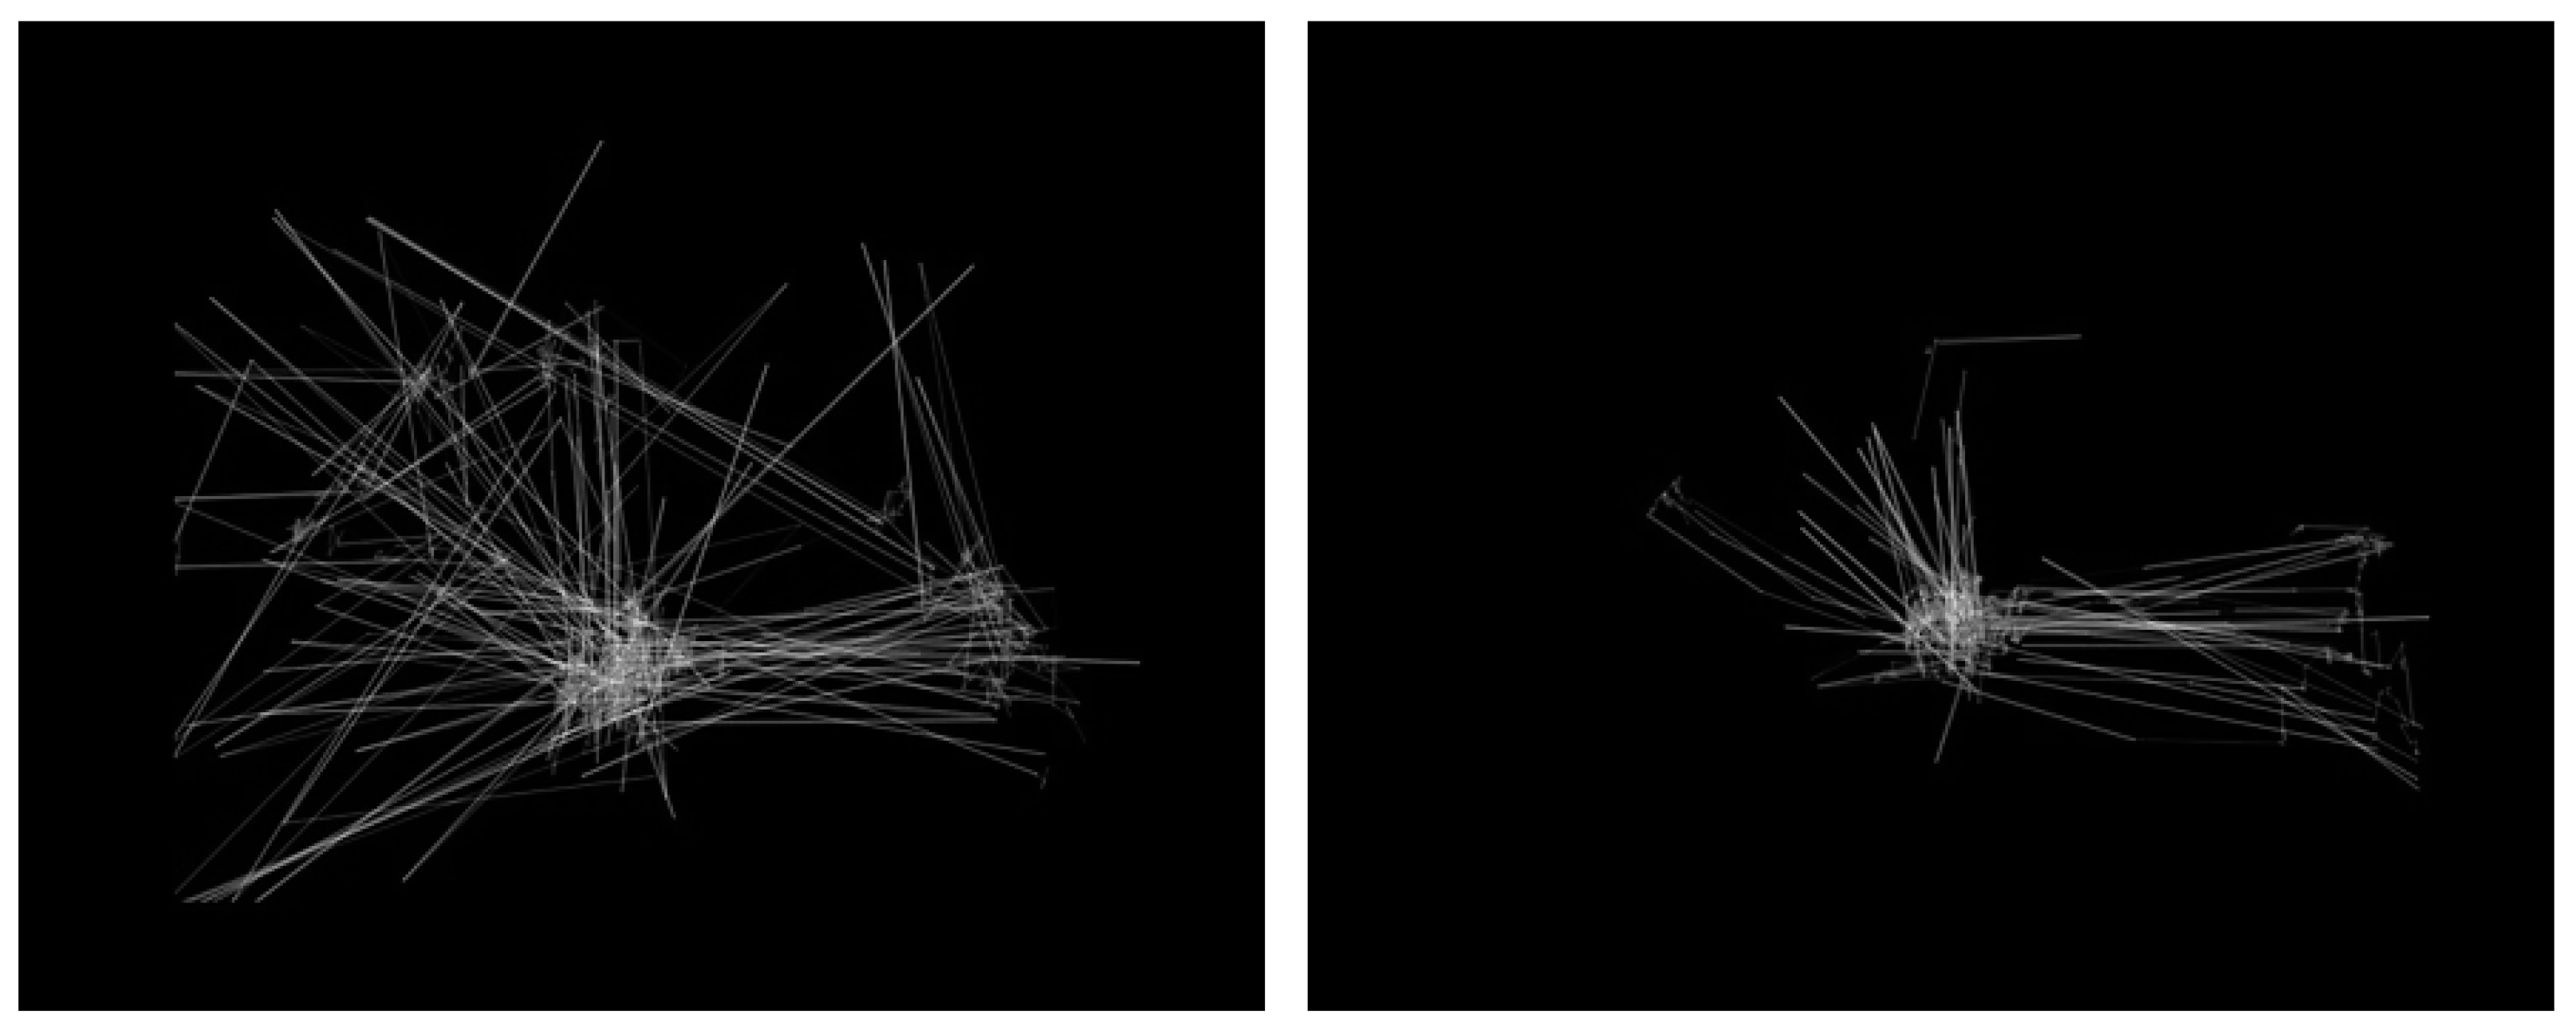

The outcome of the transformation process was an image dataset containing more than 500 images. Specifically, 328 images related to the TD participants, and another 219 images for the ASD-diagnosed. The default image dimensions were set as 640 × 480. The dataset along with its metadata files have been made publicly available on the Figshare repository [59]. Figure 4 presents two examples from the dataset.

Figure 4.

Visualization of eye-tracking scanpaths [52]. The left-sided image represents an autism spectrum disorder (ASD) sample, while the right-sided image represents the typically developing (TD).